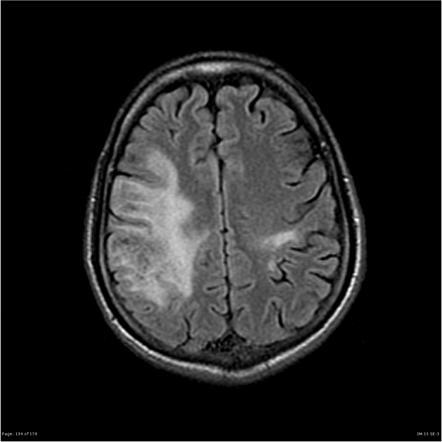

PML is a rare, often severe demyelinating disease of the central nervous system caused by reactivation of latent JC virus in patients with compromised immunity. Growing global patient populations with HIV/AIDS, multiple sclerosis, organ transplants, autoimmune diseases, and hematological malignancies significantly contribute to rising PML susceptibility.

Pharmaceutical innovation is accelerating as companies explore antiviral agents, immune-reconstitution strategies, monoclonal antibodies, and novel JCV-targeted therapies. Improved diagnostic tools-including advanced MRI, CSF testing, and next-generation JCV detection assays-are also enhancing early disease identification and treatment decision-making.

Enhanced MRI capabilities, ultrasensitive CSF viral-load assays, and molecular testing are enabling earlier detection and reducing mortality.

• High dependency on early MRI-based diagnosis